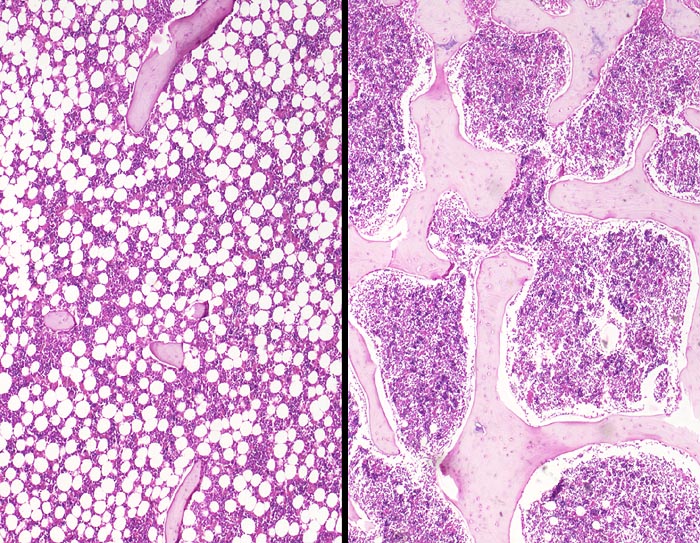

PathoPic – image database / PathoPic ID 3282 - Osteoporose (rechts im Bild Normalbefund)

Osteoporose (rechts im Bild Normalbefund)

Links im Bild die Osteoporose mit Rarefizierung und Atrophie der Spongiosabälkchen mit Störung der Mikroarchitektur des Knochens durch hochgradige Reduktion der intertrabekulären Vernetzung. Im Vergleich dazu auf dem rechten Bild ein normaler spongiöser Knochen.

72 jährige Patientin mit Rückenschmerzen und einer Schenkelhalsfraktur. Sie stirbt an einer Pneumonie.